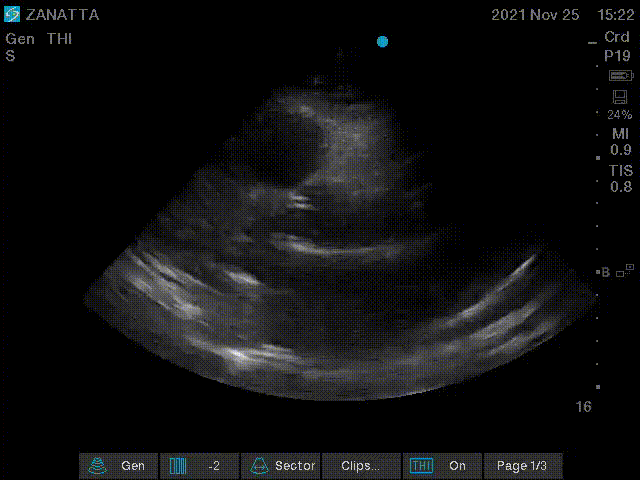

Next, you obtain an apical four chamber view and measure the TAPSE.

Apical Four Chamber